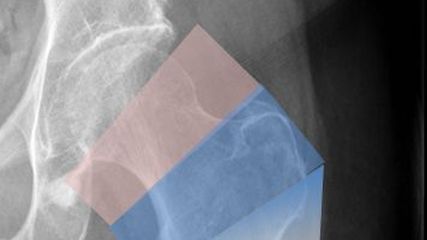

Abb. 1: Zonen der hüftnahen Oberschenkelfrakturen: mediale und laterale Schenkelhalsfrakturen (rosa Zone), pertrochantäre Frakturen (blaue Zone) und subtrochantäre Brüche (blau-weiße Zone)